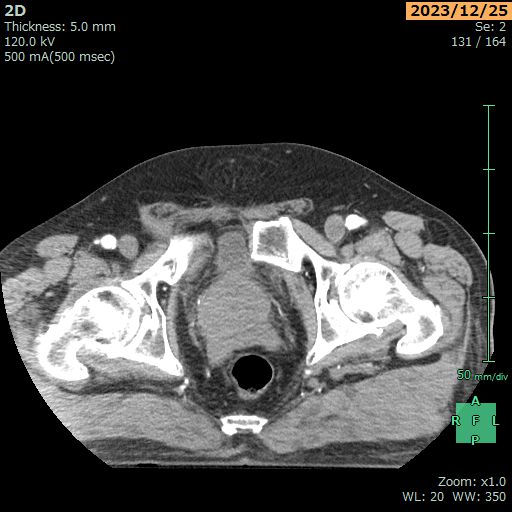

【緒言】骨盤骨折に膀胱損傷は起こりうるが、恥骨結合が離開した間隙への膀胱嵌頓は稀である。今回、術前に認識して膀胱損傷を回避できたため報告する。

【症例】70歳男性。2mの脚立から転落し、近医総合病院へ搬送。恥骨結合離開を伴った骨盤輪骨折(右仙腸関節、恥骨結合離開) AO61B2.3を認め、創外固定が行われたが、それ以上の観血的治療が困難なため、受傷2日目に当院転院 となった。前医による創外固定では恥骨結合離開が十分整復されておらず、搬送当日、創外固定を再造設する方針となった。しかし、恥骨結合離開の間隙に膀胱が嵌頓しているため、創外固定の再造設時に膀胱損傷が懸念された。恥骨上切開で後腹膜腔に到達し膀胱の展開を試みると恥骨結合が離開した間隙に膀胱が嵌っていた。膀胱を直腸側に押し下げた状態を保ちながら離開した恥骨を寄せてワイヤリングし、創外固定を造設した。

【考察】恥骨結合の離開部に膀胱が嵌頓し、膀胱圧迫、膀胱壊死また、長期合併症で膀胱ヘルニアなどが報告される。恥骨結合離開を伴う創外固定前後には膀胱嵌頓の可能性を念頭に入れる必要がある。今回の術中動画とともに報告したい。